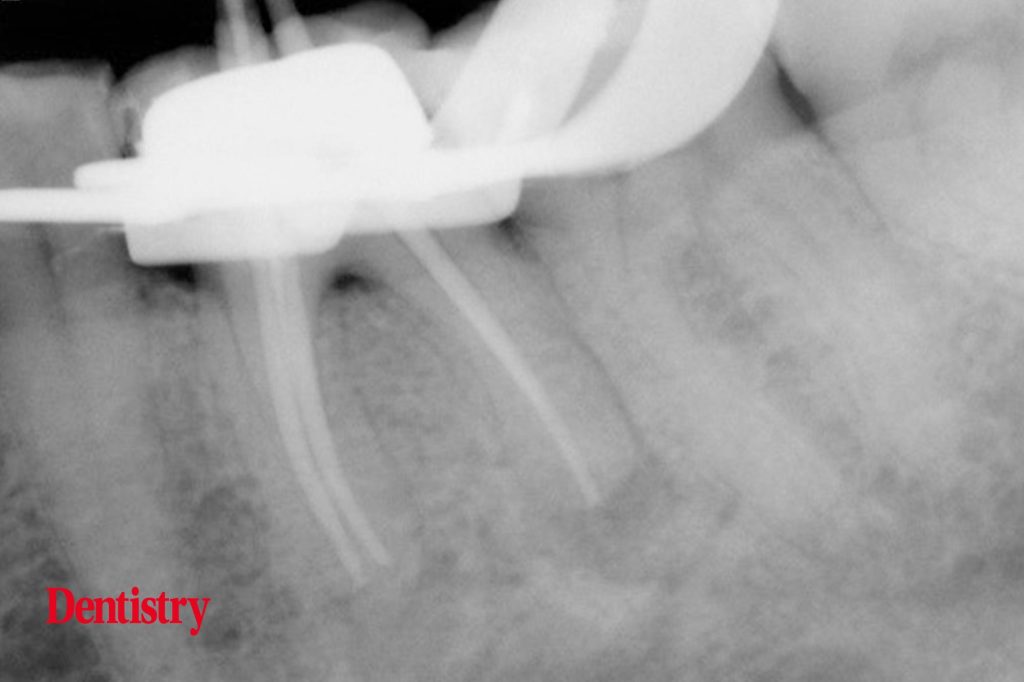

From dentistry.co.uk

Exploring Endodontics a silver point of order Dentistry Silver Point Endodontics The first step in removing a silver point is to carefully remove any core material from around the point. Silver point removal the relative ease of removing a silver point is based on the fact that chronic leakage reduces the seal and hence, the lateral retention. Clinicians frequently encounter endodontically treated teeth that contain silver points within their roots. However,. Silver Point Endodontics.